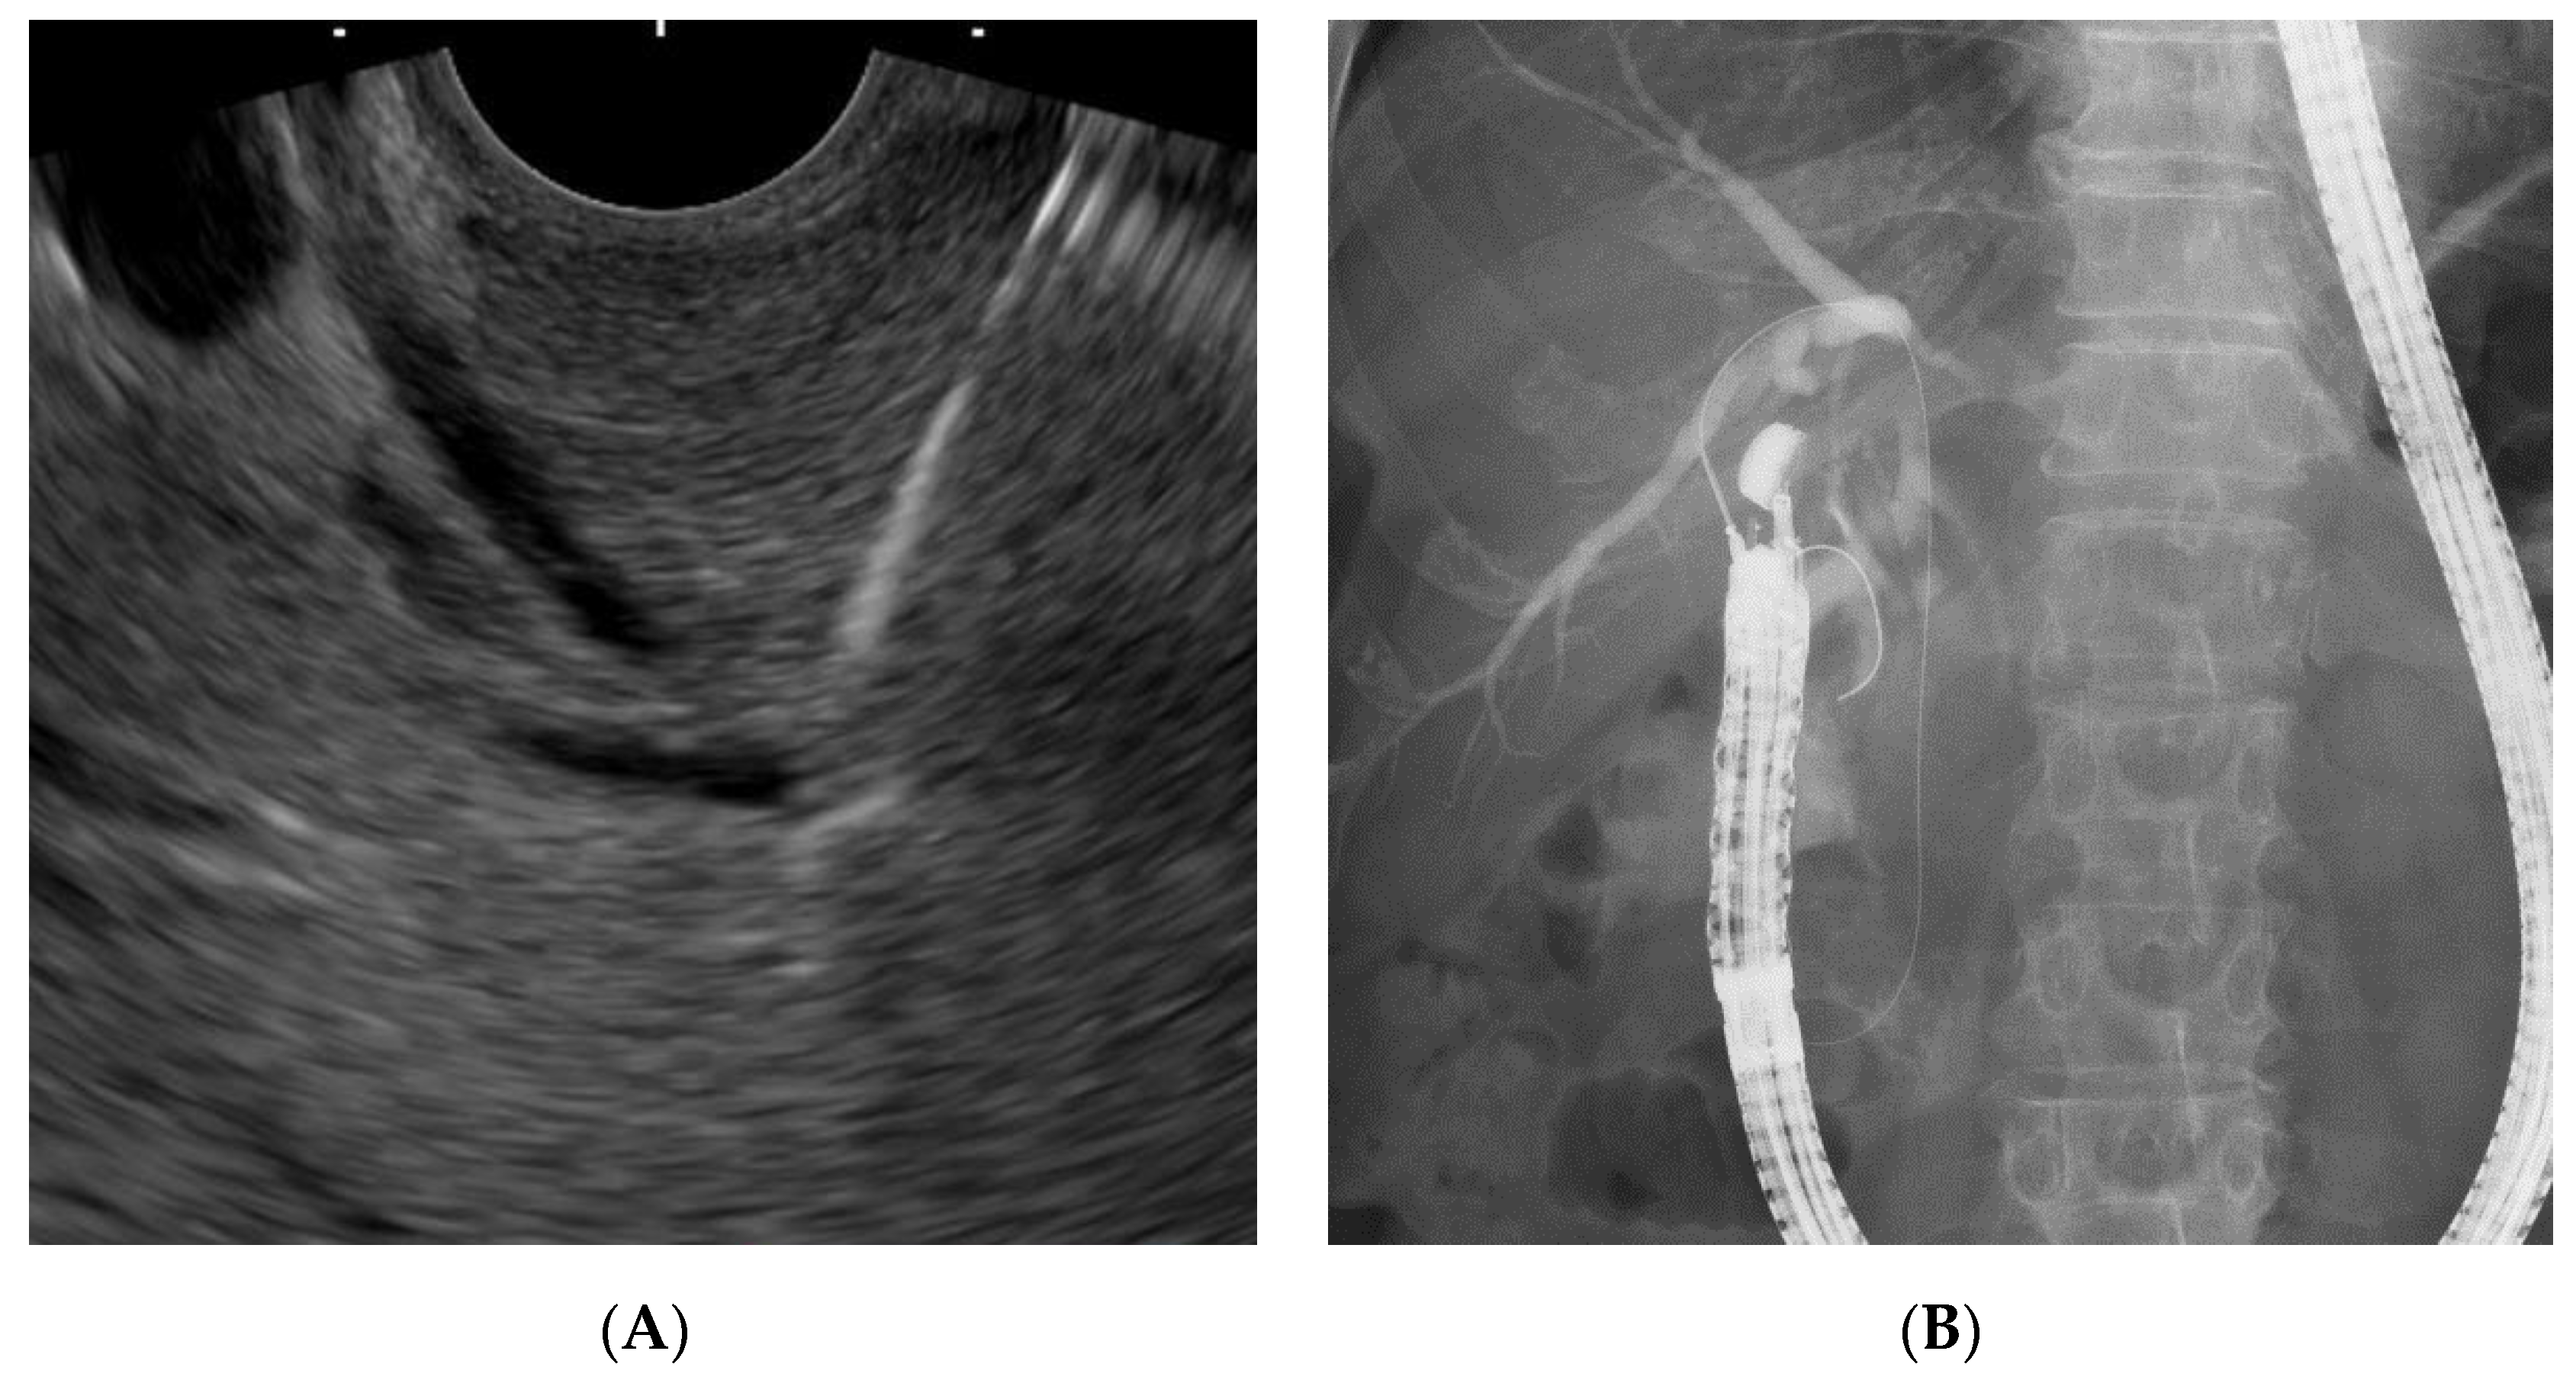

2.3. EUS-RV Procedure

2.4. Our EUS-RV Method Regarding Approach Routes and Needle Sizes

2.5. Biliary Cannulation Methods during EUS-RV